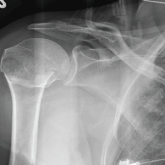

Give Her a Shoulder to Cry on

- Author:

- Nandan R. Hichkad, PA-C, MMSc

Publish date: May 13, 2019